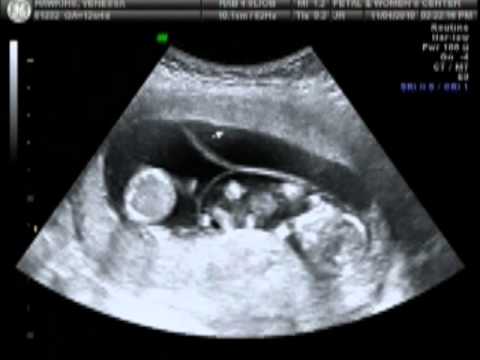

I found out about a week before Jordan turned 1 that we were expecting again! It was surprising how quick it happened with me still exclusively BF him & with there being 8 years between Haley & Jordan. We were feeling a bit nervous at the thought of having 2 kids so close in age & having 3 kids by the age of 27 & with us both being in school. I thought we can do this, we have all the baby supplies we need since we still had all of J's baby stuff. I went to my first OB appointment at 8 weeks, I lost 13 pounds in 2 weeks from the morning sickness so I got 2 prescriptions for the nausea. When he did the pelvic exam he mentioned my uterus felt slightly big for 8 weeks & I said don't say that my grandma had twins! He said it's common for it to feel a little large & not to worry. 2 weeks later my uterus was already bulging in my lower belly just a few inches from my navel. I told Ronel that I had a feeling that there might be twins in there, but we thought having 2 babies back to back might make it stretch faster. At my 12 week check up a student was present with my Dr & he did the doppler to look for the baby's heartbeat. He pushed it down hard(since at that stage your uterus is supposed to be lying deep in your pelvis) & that made the "baby" wiggle! It kinda scared me to be honest, I didn't think you could feel a baby move that early. Looking back i feel bad because that wiggle I felt was one of my little guys getting pushed on! I told him I really felt bigger than I should & I was worried it could be twins. He told me many women think that and my US was the next day, so not to worry. On November 4th, 2010 I got the shock of a lifetime. I went in for my elective 12 week ultrasound to check for down syndrome/spina bifida with Jordan since I was expecting just a 20 minute US. The second she touched the probe to my stomach I saw 2 babies I said "Oh my god it's twins isn't it?" she moved it around for a few seconds & replied "Oh honey... your having triplets!" I told her there's no way there's 3 in there & she must be counting the same one twice, I wasn't on fertility drugs it doesn't happen spontaneously right??? WRONG! She then counted them out for me as you can see in the clip I will post. (It's a clip of the recording of the US I had, so happy they do that with everyone so I can re-live the shock of seeing 3 in there forever. lol.) I proceeded to cry hysterically(which I don't do hardly ever) and mumble "I don't have 3 arms, I don't have 3 boobs, how the hell am I supposed to take care of 3 babies?!?!". Poor little 14month old Jordan didn't even realize how his life, & mine, changed that moment. Luckily one of the receptionists took Jordan so I could get a 2 hour ultrasound of all the babies. I left in a state of shock to say the least! I had to pick up Ronel from work right after so I held off on calling him. I called my best friend Ashley first & cried to her that definitely helped. When Ronel got in the car I handed him the US pic & asked if he noticed anything. He said "it's a boy?" I replied "no, do you notice the letters?" he said "are those the body parts?" I replied "no, each letter represents each baby" he said "but there's 3 letters?!" I replied "yes because there's 3 babies". We were both in shock for weeks! We're still amazed that WE had triplets.